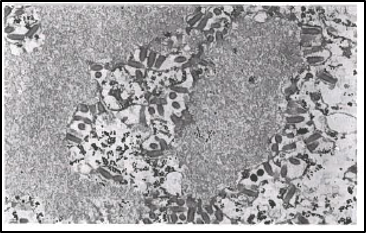

Microscopic image of rabies virus in a fox brain.

– Image provided by LSU Diagnostics

According to the Centers for Disease Control, rabies testing should only be performed in accordance with the established national standardized protocol by a qualified laboratory that has been designated by the local or state health department. The direct fluorescent antibody test (dFA) is the test most frequently used to diagnose rabies. This test requires brain tissue from animals suspected of being rabid and can only be performed post-mortem. This test has been thoroughly evaluated for more than 40 years and is recognized as the most rapid and reliable of all the tests available for routine use. Other tests for diagnosis and research such as electron microscopy (EM), histologic examination, immunohistochemistry (IHC), RT-PCR, and isolation in cell culture are useful tools for studying the virus structure, histopathology, molecular typing, and virulence of rabies viruses.